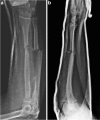

Treatment of a segmental defect in open radial and ulnar shaft fractures using rhBMP-2 and iliac crest bone graft: a case report